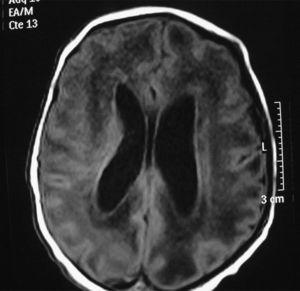

En la bioquímica se observaron 243 U/l de aminotransferasa glutamicoxalacética (GOT), 218 U/l de aminotransferasa glutámico pirúvica (GPT) y 258 U/l de gammaglutamil transpeptidasa. El estudio de coagulación fue normal. La ECO cerebral mostró ventriculomegalia leve, un parénquima cerebral hiperecogénico y vasculopatía de las arterias tálamo-estriadas. No hubo signos de hemorragia. La RM cerebral mostró ventriculomegalia y alteración difusa de la señal en sustancia blanca (fig. 2). El electroencefalograma mostró un trazado normal. La ECO abdominal mostró hepatoesplenomegalia homogénea. El electrocardiograma y la ecocardiografía fueron normales. Se realizó serología para sífilis, toxoplasma, VIH y parvovirus que resultó negativa y serología para CMV, IgM e IgG, que resultó positiva. La punción lumbar fue de 15×106 cél/l, la glucosa fue de 61 mg/dl, las proteínas fueron de 90 mg/dl. El cultivo de orina a los 7 días de vida fue positivo para CMV. La PCR para CMV en sangre y el líquido cefalorraquídeo fueron positivos. El fondo de ojo fue normal. Los potenciales evocados auditivos mostraron ausencia de respuesta a >110 dB en el oído izquierdo (OI) y normalidad en oído derecho (OD). En el primer día y en el tercer día de vida, la niña precisó transfusión de plaquetas, y requirió alimentación por sonda nasogástrica hasta el octavo día. También se inició ventilación no invasiva (presión positiva continua en la vía respiratoria nasal) hasta la semana de vida por pausas de apnea con bradicardia. Se decide no iniciar tratamiento con ganciclovir al considerar que no mejoraba el pronóstico de su enfermedad y por presentar importantes efectos secundarios. Se le da de alta a los 15 días de vida.

Figura 2. Resonancia magnética cerebral en la que se aprecia ventriculomegalia y alteración difusa de la sustancia blanca.